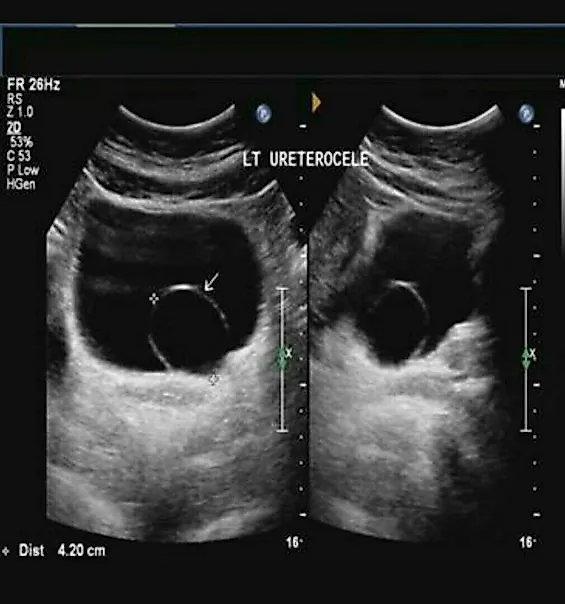

1. Ультрасонография является лучшим первичным этапом диагностики уретероцеле Ультразвуковое исследование назначают в качестве контрольного обследования для оценки внутриутробного развития плода или при диагностике инфекции мочевыводящих путей Эта методика позволяет визуализировать верхние мочевыво-дящие пути и выявить гидронефроз Она также позволяет обнаружить кистозное объемное образование в нижней части дистального отдела мочеточника и в проекции мочевого пузыря